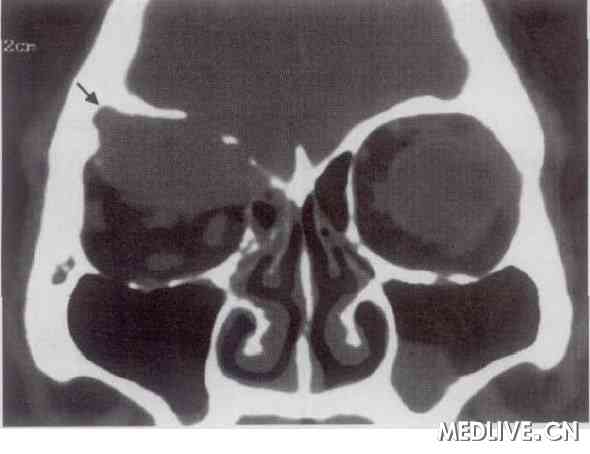

患者男性,35 岁,因左眼球突出3个月,于2004年2月到我院就诊。全身体检未见异常。眼部检查:经国际标准对数视力表查视力右眼裸眼视力0. 5,不能矫正。左眼球向前突出4 mm,各方向运动无明显受限,眼底未见异常。实验室检查:血清免疫球蛋白及尿Bence Jones蛋白均为阴性。胸部X线检查正常。CT扫描:显示左眼眶内软组织肿块影,眶上壁可见骨破坏(图1)。临床诊断:左眼眶内肿瘤。于同年3月14日全身麻醉下行左眶内肿瘤切除术。术中见肿瘤组织呈紫红色,质脆,眶上壁有骨质破坏。病理学检查:光镜下可见瘤细胞呈多角形, 胞质丰富,核卵圆形、深染、偏位,细胞有一定的异型性。肿瘤组织经免疫组织化学染色可见浆细胞抗体阴性,白细胞共同抗原阴性;B 细胞单克隆抗体:CD20阴性,CD79α阴性;T细胞单克隆抗体:CD3阴性,CD45RO阴性;κ轻链单克隆抗体阳性;λ轻链单克隆抗体阴性。病理学诊断为髓外浆细胞瘤(extra medullaryp lasmacytoma,EMP)。术后给予放疗,剂量为40 Gy。随访17个月无复发。

图1 眼眶髓外浆细胞瘤患者,CT扫描示右眼眶内软组织块影,边缘清楚,压迫邻近骨质呈骨破坏改变(箭头)

近年来,影像学检查手段的完善使其成为EMP的重要辅助诊断方法之一。EMP的CT诊断对本病有一定价值, 主要CT表现为局部软组织肿块影, 边缘较清晰,推压邻近结构致其变形、移位,较常见征象是邻近骨质破坏。Corwin和Lindberg[3]报道12例EMP中有8例出现骨破坏,许健等[4]报道3例均有骨质破坏,梁自民[5] 报道11例中有6例骨质破坏。本组2例发生于眼眶者均有邻近眶骨受侵犯。